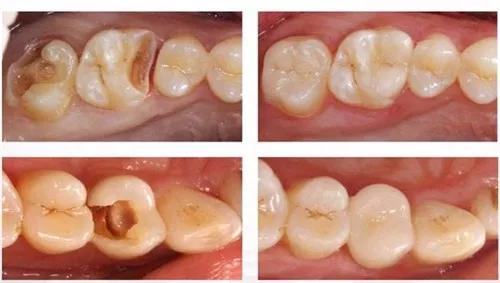

症状: 蛀牙,牙齿龋坏;坏了一点的;没有伤到神经,没有自发疼痛的。像这种只需要补牙就行了。

应对方式: 简单补牙即可

症状: 龋坏缺损较大;有自发疼痛,刺激疼;这种说明已达牙神经,神经已经感染发炎,无法挽回,需要做根管治疗,然后再补上。

应对方式: 根管治疗+补牙,前牙根管+普通树脂,后牙根管+进口树脂

症状: 龋坏、缺损占牙冠一半以上了。这种情况做完神经治疗后,需要打桩做牙冠。

应对方式: 根管治疗+打桩+牙冠